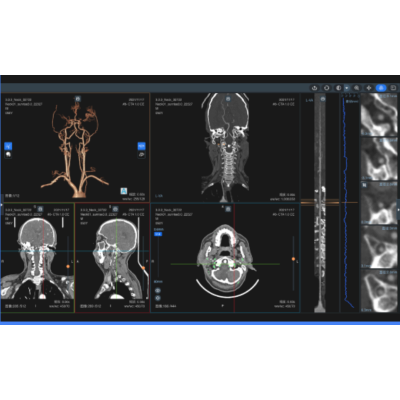

头颈/颅内血管辅助分析(CTA/MRA)

血管智能分析产品能够全自动、智能化的高效完成血管3D重建、血管全程精确追踪、曲面像拉直像血管2D分析,病变血管精准定位,狭窄部位智能识别、高亮标记,多模态、多平面狭窄关联定位,狭窄度精确评估等功能。